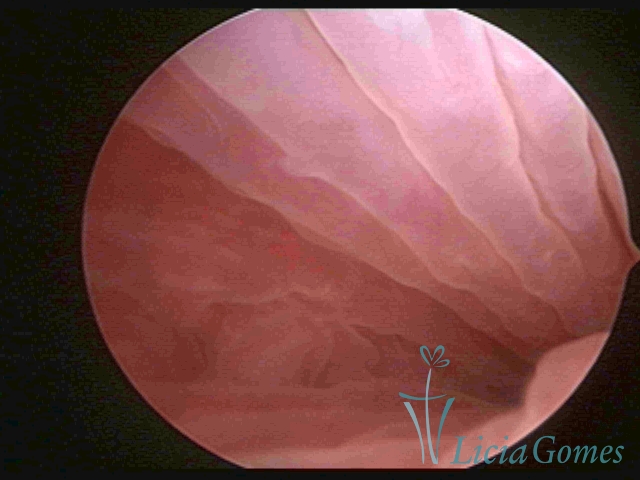

Primeira porção ou setor proximal ou setor inferior:

Durante a fase proliferativa, encontramos muco claro e cristalino pouco aderente à óptica. As criptas e as papilas apresentam-se um pouco edemaciadas e vascularizadas, micro vesicular, lembrando cachos de uva.